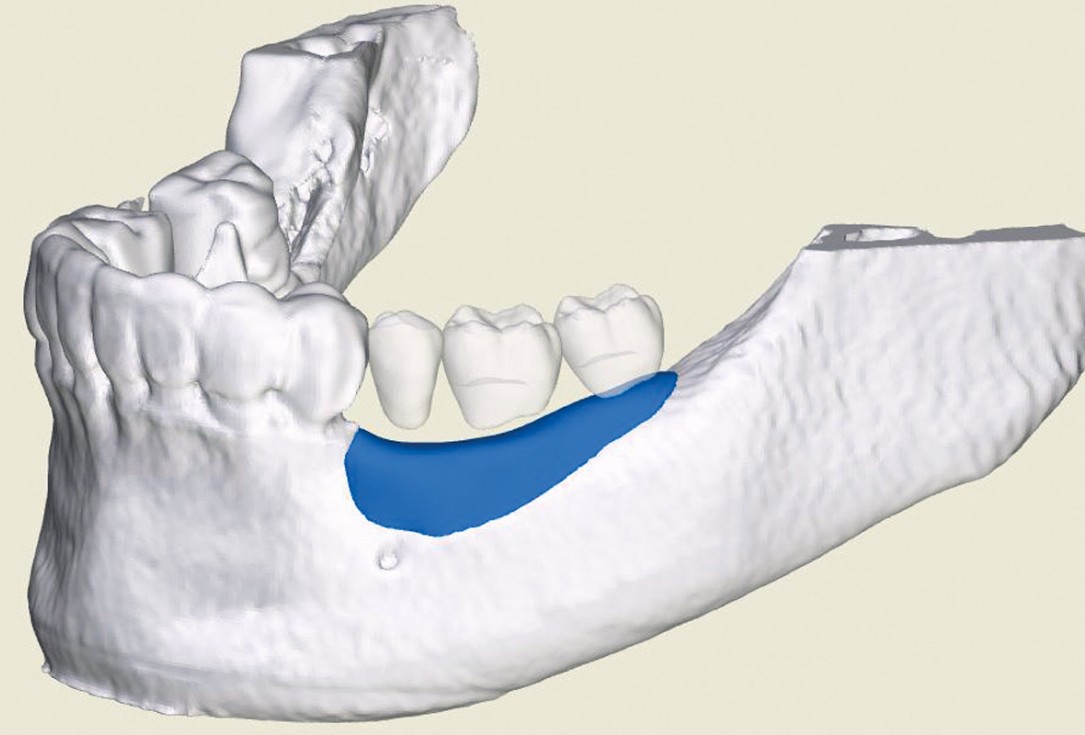

03/12 - 3D reconstruction of the bone defect and planned maxgraft® bonebuilder

Ridge augmentation in the mandible with maxgraft® bonebuilder in a free-end situation - Dr. Dr. Dr. O. Blume